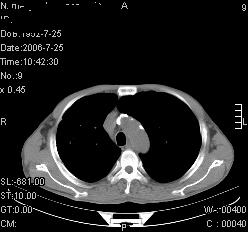

患者,男,54岁,咳嗦,咳痰20天。抗炎治疗2周。现esr76mm/h,目前患者症状明显好转,但发现两次ct片未见明显变化。两次分别做与7.25、7.31。第一次诊断右肺上叶炎症累计胸膜。大家看,从影像上内排除结核吗?

结核的可能性非常大,右上肺病变应该考虑干酪性肺炎。理由:

1.纵隔内多发淋巴结肿大。

2.esr76mm/h。

3.虽经抗炎治疗肺窗病灶有所吸收、减小,但纵隔窗病灶形态、密度、范围无明显变化。如果是单纯的大叶性肺炎,“抗炎治疗2周,目前患者症状明显好转”病灶应该基本消散了,至少也处于吸收消散期,密度变淡、范围变小。同时本病例所示其内的密度不均匀,见多发大小不一空洞样影也不符合大叶性肺炎吸收消散期表现。

病灶特点:片状 索条 结节混杂影,部分融合,密度不均,广泛累及相应胸膜.

临床治疗;二周未吸收.但症状好转.

多考虑:肺结核.